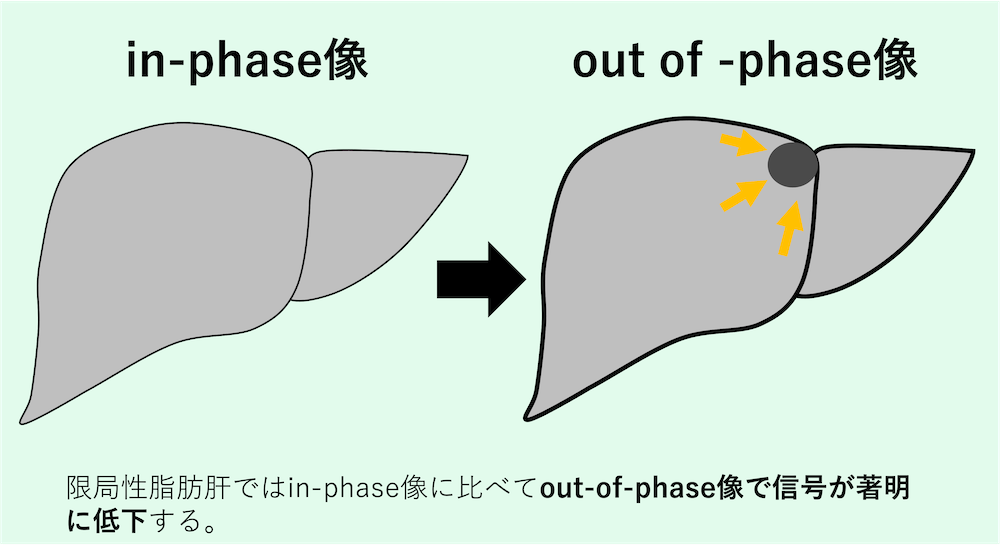

MRI、特にケミカルシフトイメージング(chemical shift imaging)は、脂肪の含有を証明する上で最も感度が高い手法である。

- in-phase像:水と脂肪の信号が加算される。

- out-of-phase像:水と脂肪の信号が打ち消し合う。

限局性脂肪肝では、in-phase像に比べてout-of-phase像で信号が著明に低下する。逆に、限局性非脂肪肝は周囲の脂肪肝がout-of-phase像で信号低下を起こす中で、相対的に高い信号を維持する領域として認識される。